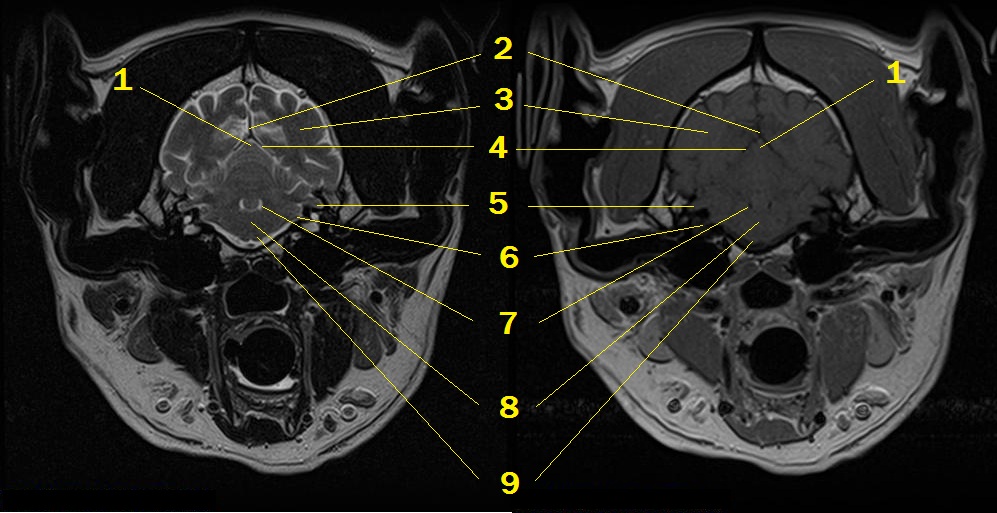

MRI anatomy 11

Q. Identify the structures labeled below:

A.

1. cerebellar vermis

2. falx cerebri

3. occipital lobe

4. osseum cerebella tentorium

5. paraflocculus of cerebellum

6. vestibulocochlear nerve - cochlear nuclei

7. 4th ventricle

8. medulla

9. pyramid